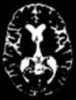

Progressive brain atrophy

Cerebral atrophy is a common feature of many of the diseases that affect the brain. Atrophy of any tissue means a decrement in the size of the cell, which can be due to progressive loss of cytoplasmic proteins. [Source: Wikipedia ]